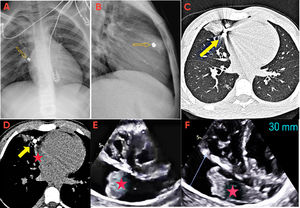

Varón de 13 años que acude a urgencias tras recibir un impacto torácico por un perdigón. Presenta disnea y herida penetrante de 0,5cm en el cuarto-quinto espacio intercostal derecho, con enfisema subcutáneo. La radiografía de tórax evidencia el proyectil (fig. 1A, B, flecha) y la tomografía computarizada muestra hemopericardio, hemorragia pulmonar y neumotórax (fig. 1C, D).

Ingresa en la unidad de cuidados intensivos pediátrica, donde se completa el estudio con ecocardiografía, que muestra un derrame pericárdico grave (fig. 1E, estrella), con signos incipientes de compromiso hemodinámico, y una masa hiperecogénica oscilante, sugestiva de hematoma pericárdico (fig. 1F y vídeo S1).

El proyectil estaba alojado en el parénquima pulmonar junto a la pleura mediastínica, en la transición aurícula derecha-orejuela (fig. 1B). Tras la valoración multidisciplinar, se decidió una actitud conservadora por su estabilidad radiológica, resolución del hemopericardio y mejoría clínica.